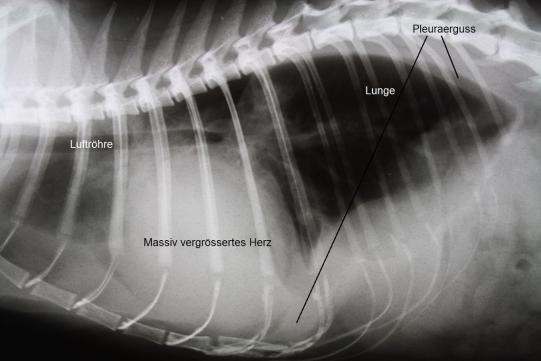

Alle Befunde weisen darauf hin, dass Schnurrli eine Blockade der Schenkelarterien durch ein Blutgerinnsel aufweist (Sattelthrombus) - meist ist dieses Problem durch eine primäre Herzerkrankung mit folgender Bildung von Blutgerinnseln bedingt (siehe Fall 54, Oktober 2012 ). Ein Röntgenbild bestätigt, dass das Herz der Katze enorm gross ist und sich im Brustkorb ein Erguss gebildet hat - beides typische Befunde bei Herzproblemen.